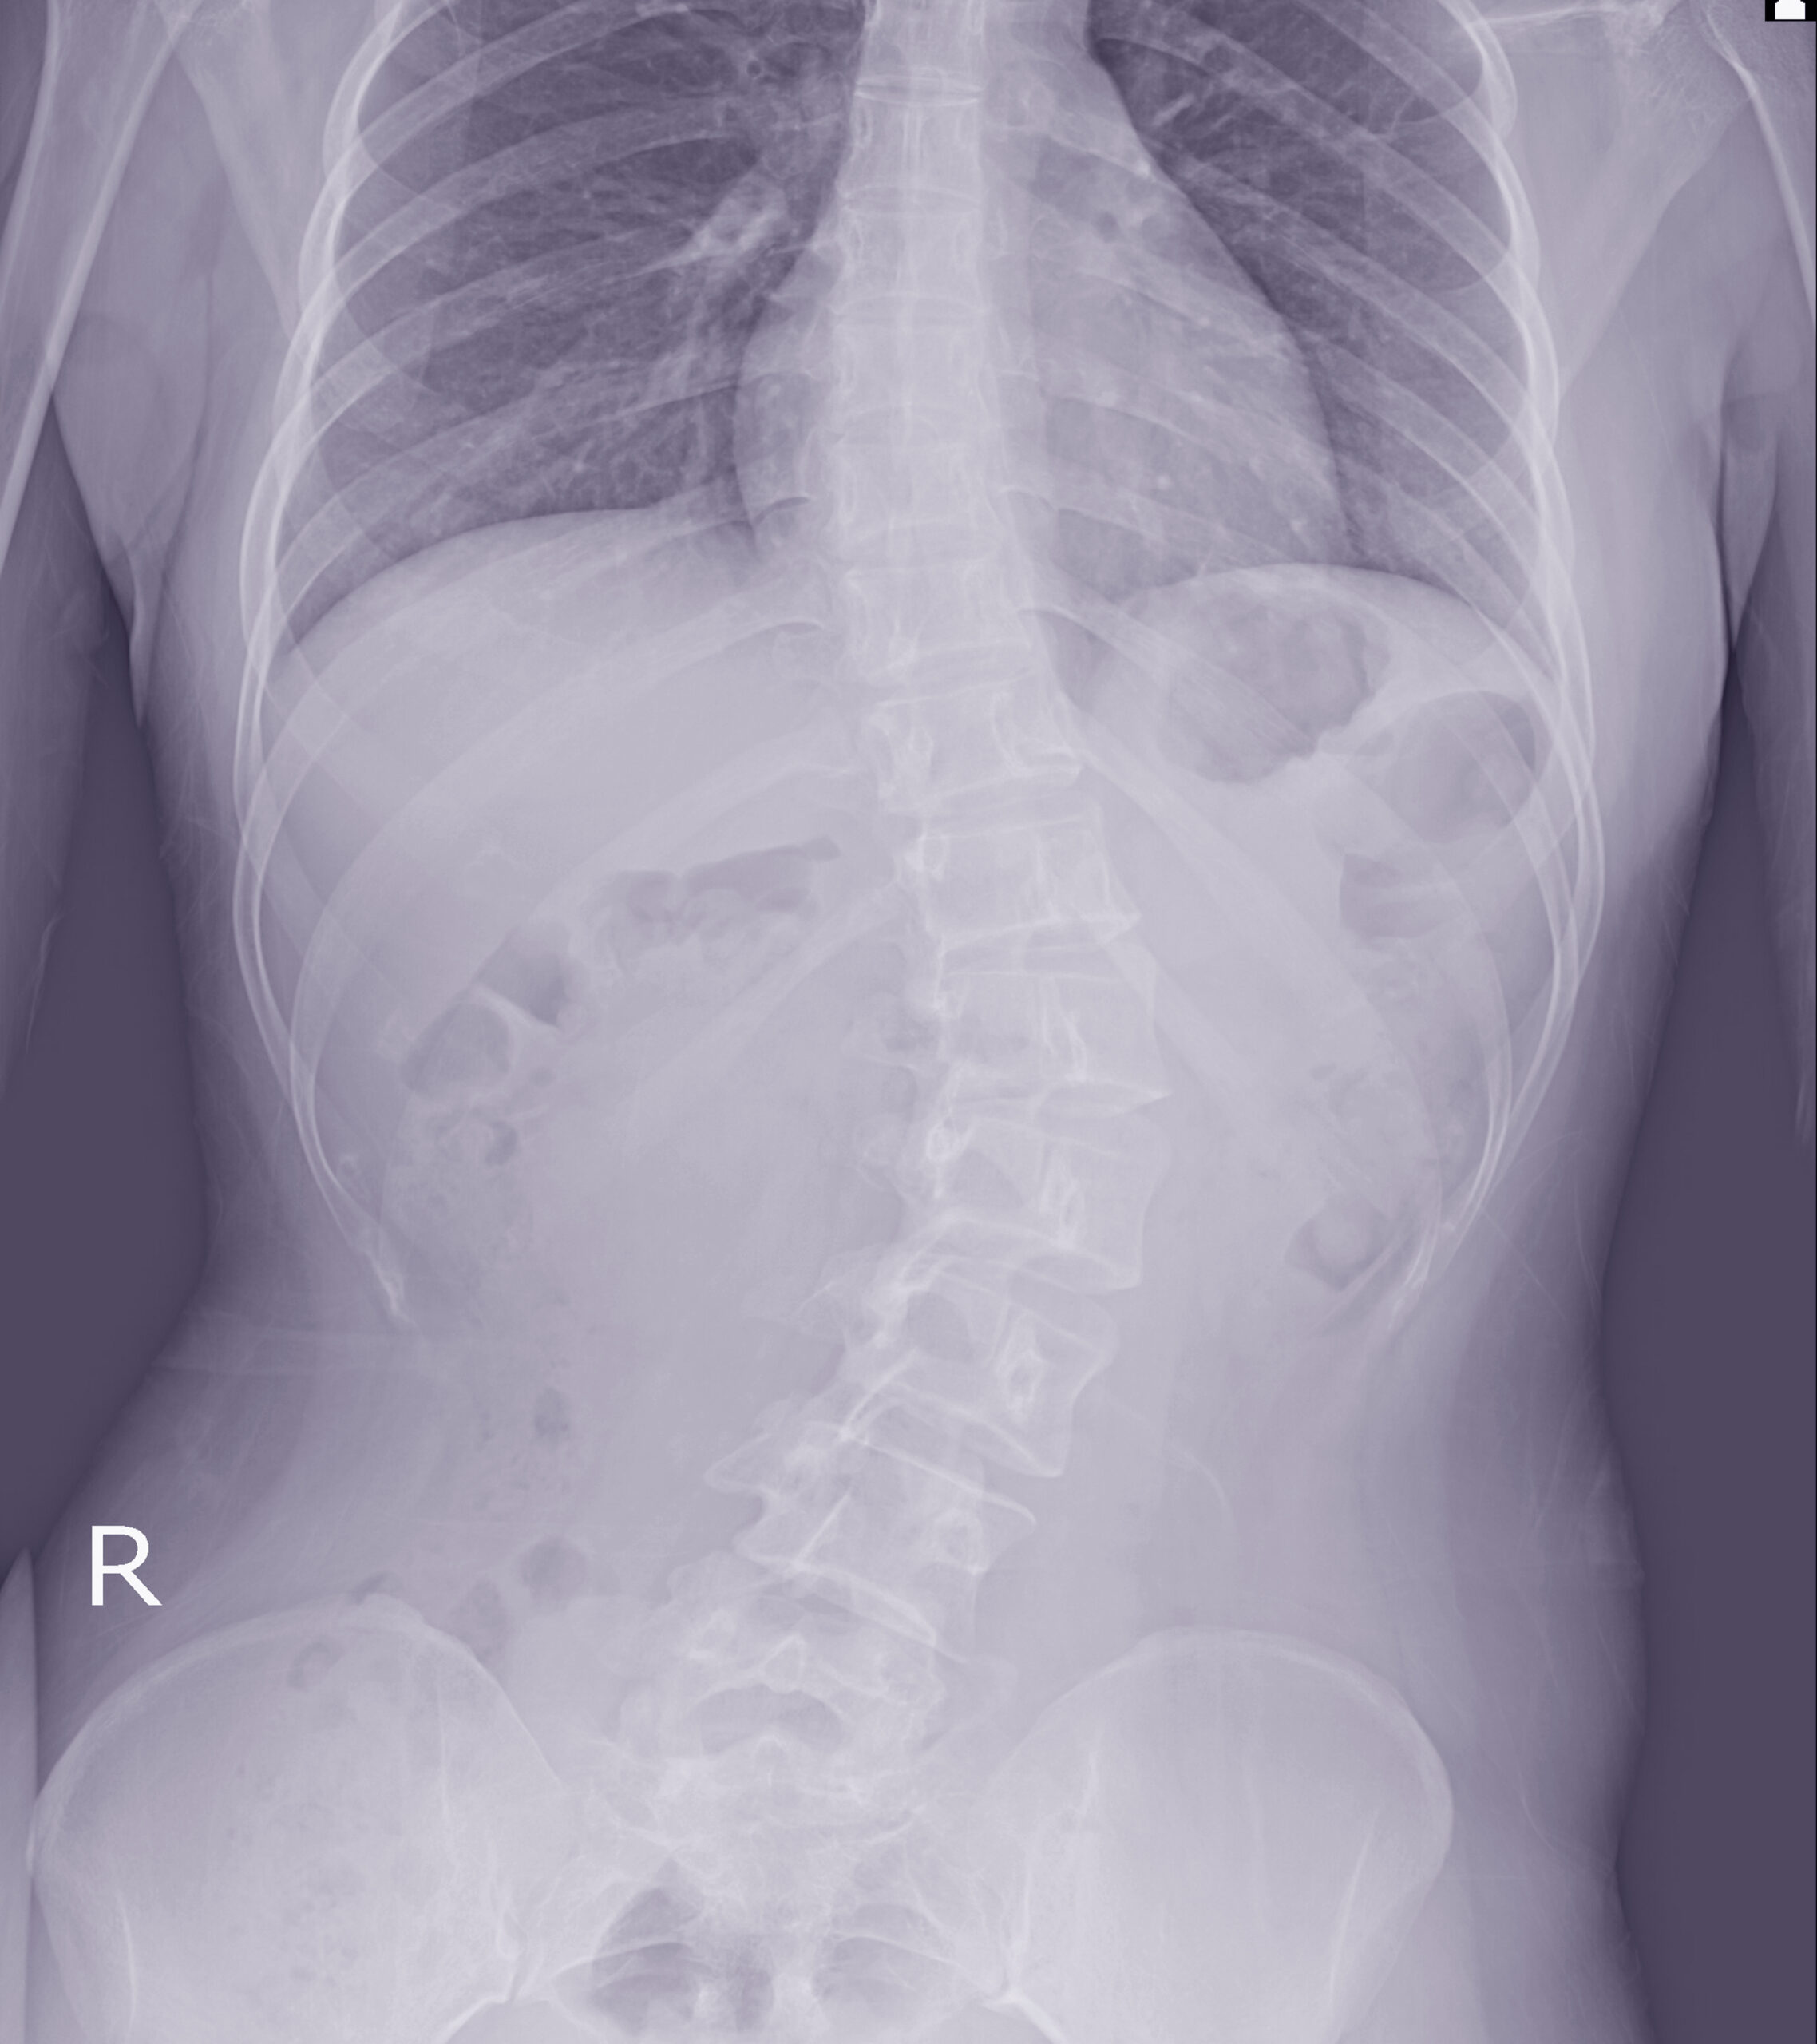

O manejo perioperatório da escoliose neuromuscular é um dos maiores desafios da ortopedia e neurocirurgia pediátrica. O sucesso do tratamento cirúrgico depende de um planejamento detalhado, da integração entre diferentes especialidades médicas e de cuidados pós-operatórios específicos, que reduzem complicações e promovem uma recuperação segura e eficaz.

O procedimento mais utilizado para pacientes com escoliose neuromuscular é a artrodese posterior da coluna, que visa corrigir a deformidade e estabilizar a coluna. A cirurgia tem duração média de seis horas, podendo variar conforme a gravidade da curva, presença de obliquidade pélvica e necessidade de fixação até a pelve.